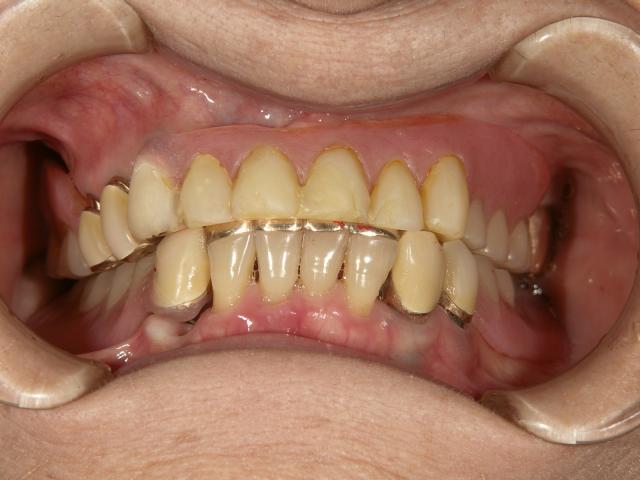

テレスコープタイプの入れ歯(上顎)

2007/04/27

70代女性 担当:院長

義歯が磨り減ってよく噛めない。

唇を噛んでしまう。

前歯の部分が見えないので、自然に見えるようにして欲しい。

術前space術後

術前 術後

1年ほどかけて咬合を挙げてから新義歯作成しました。

新義歯作成 新義歯作成

術後の自然観比較してください!